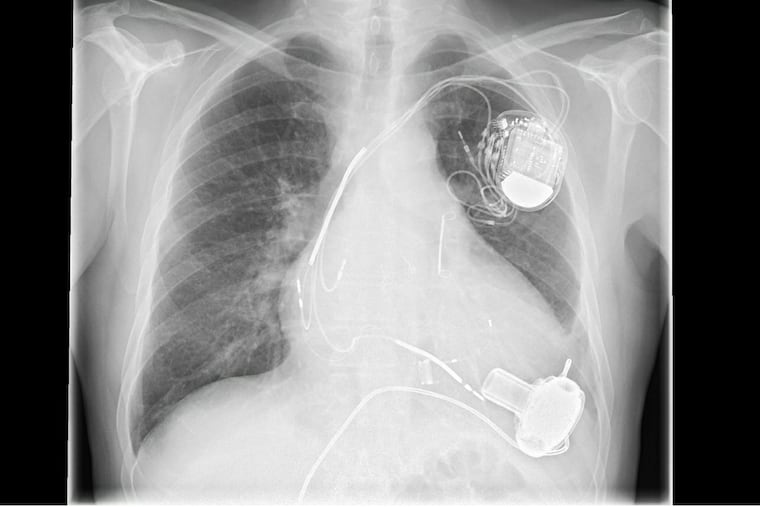

He had had a pacemaker implanted at Temple Hospital just the week before and a visiting nurse was sent to check on him after his operation. The nurse had called and said the man was short of breath and seemed to be retaining fluid just four days after his pacemaker operation.

The next day, I performed an echocardiogram — or cardiac ultrasound — chest X-ray, and lab studies. His echocardiogram showed newly depressed heart function, with his heart squeezing at only half its usual strength. His chest X-ray also confirmed congestive heart failure.